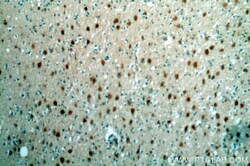

Immunohistochemistry

16632-1-AP IHC